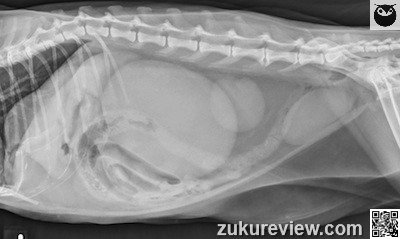

Which organ is abnormal in these radiographs from a 13-year-old male neutered cat?

The right kidney is markedly enlarged, with a rounded shape. It is distorting the abdominal wall on the v/d projection and displacing the ascending and transverse colon medially and ventrally. This was a perinephric pseudocyst, which is often associated with chronic renal disease, but is often asymptomatic in itself.

The left kidney also has an abnormal shape, with reduced length and increased width. There is also spondylosis deformans at the L5-6 intervertebral disc space, which is an incidental finding.